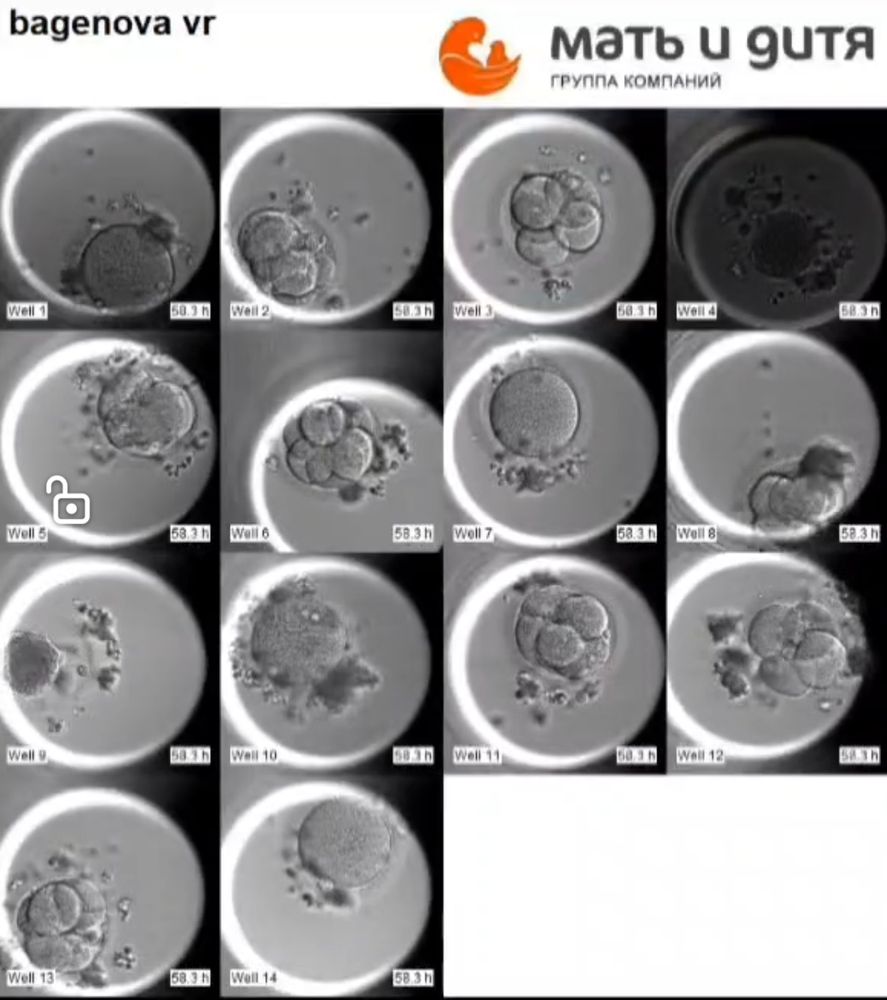

6 эмбрионов к 6 дню )

Veronika , Они сами присылают видео ) Это в комплекте с инкубатором который я покупала, они потом присылают видео как эмбриошки развивались

Как здорово все это видеть хотя бы на картинке) обязательно сохраните где-нибудь у себя) пусть у вас все получится 🙏💫